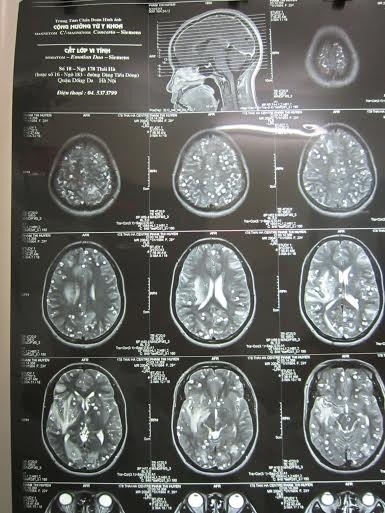

Giun đũa chó ẩn nấp trong não

Bệnh viện Nhiệt đới trung ương mới tiếp nhận một trường hợp bệnh nhi bị viêm não do ấu trùng giun từ món nem chua.

Theo người nhà bệnh nhân, sau nhiều ngày sốt, buồn nôn, đau đầu, bệnh nhân rơi vào trạng thái lơ mơ. Bệnh viện tỉnh nghi ngờ bị viêm não nên đưa bệnh nhân ra tuyến trung ương. Sau khi tiến hành các xét nghiệm, bác sĩ cho biết bệnh nhân bị viêm não do giun đũa chó. Người nhà của bệnh nhi mới nhớ ra trước khi bị ốm, bệnh nhân có ăn nem chua với rau sống.

Bác sĩ nghi ngờ ấu trùng của giun đũa chó có trong các thức ăn chưa được nấu chín đã theo đường ăn uống chui vào cơ thể rồi di trú ở não.